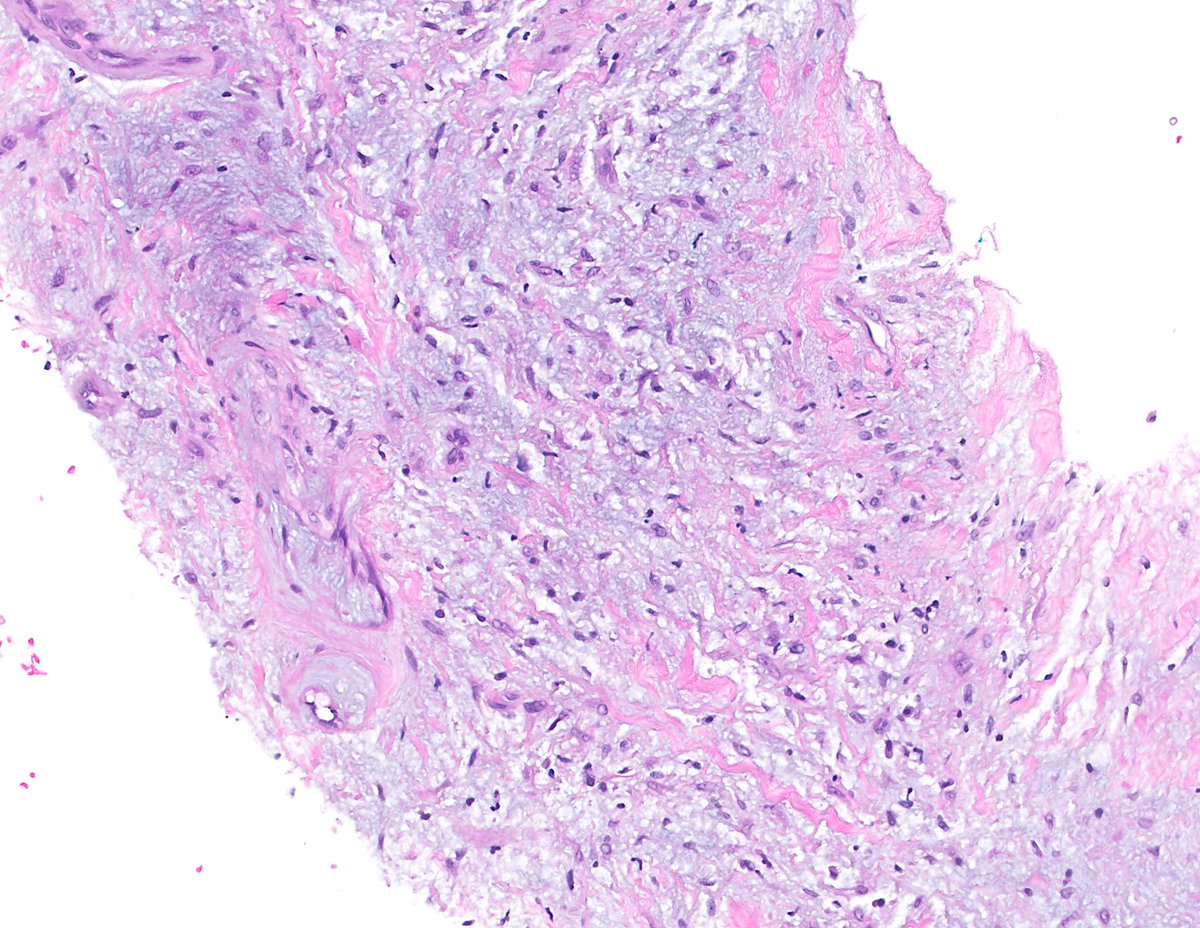

Thyroid mass in 20yo ♀️ with FAP, Diagnosis? a) Columnar Cell Papillary Thyroid Carcinoma b) Metastatic Ductal Carcinoma c) Metastatic Colorectal Carcinoma d) Cribriform-Morular Thyroid Carcinoma (CMTC) #ENTPath #Pathology #PathTwitter #Thyroid #PediPath

Thyroid mass in 20yo ♀️ with FAP,  Diagnosis?

a) Columnar Cell Papillary Thyroid Carcinoma

b) Metastatic Ductal Carcinoma

c) Metastatic Colorectal Carcinoma

d) Cribriform-Morular Thyroid Carcinoma (CMTC)